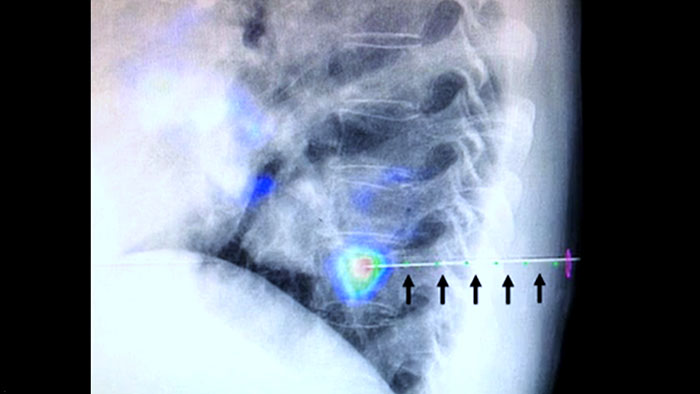

XperGuide fournit un guidage par imagerie en temps réel très précis de chaque aiguille vers une position cible en superposant les trajectoires préplanifiées avec l’imagerie fluoroscopique.3